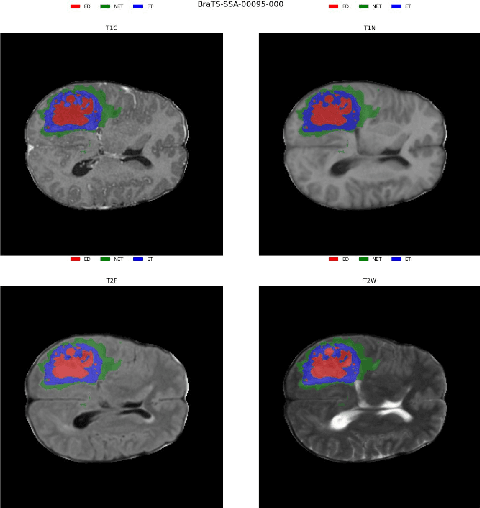

Abstract:Identifying key pathological features in brain MRIs is crucial for the long-term survival of glioma patients. However, manual segmentation is time-consuming, requiring expert intervention and is susceptible to human error. Therefore, significant research has been devoted to developing machine learning methods that can accurately segment tumors in 3D multimodal brain MRI scans. Despite their progress, state-of-the-art models are often limited by the data they are trained on, raising concerns about their reliability when applied to diverse populations that may introduce distribution shifts. Such shifts can stem from lower quality MRI technology (e.g., in sub-Saharan Africa) or variations in patient demographics (e.g., children). The BraTS-2024 challenge provides a platform to address these issues. This study presents our methodology for segmenting tumors in the BraTS-2024 SSA and Pediatric Tumors tasks using MedNeXt, comprehensive model ensembling, and thorough postprocessing. Our approach demonstrated strong performance on the unseen validation set, achieving an average Dice Similarity Coefficient (DSC) of 0.896 on the BraTS-2024 SSA dataset and an average DSC of 0.830 on the BraTS Pediatric Tumor dataset. Additionally, our method achieved an average Hausdorff Distance (HD95) of 14.682 on the BraTS-2024 SSA dataset and an average HD95 of 37.508 on the BraTS Pediatric dataset. Our GitHub repository can be accessed here: Project Repository : https://github.com/python-arch/BioMbz-Optimizing-Brain-Tumor-Segmentation-with-MedNeXt-BraTS-2024-SSA-and-Pediatrics